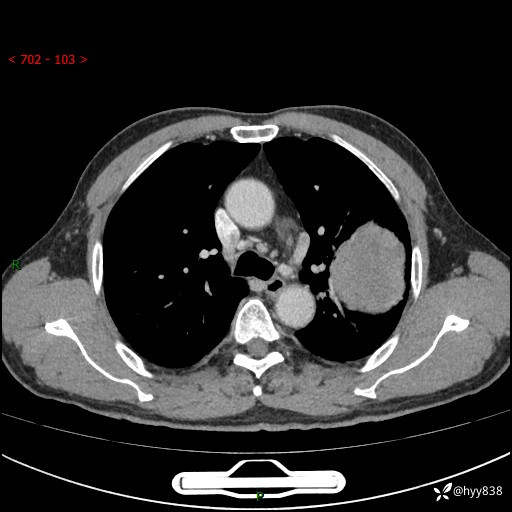

68岁/男,发现左下肺占位5天。如此大的肿块,患者竟然没有症状---结果公布~

【患者信息】:68岁/男

【主诉】:检查发现左下肺占位5天。

【现病史及既往史】:患者于4天前外院行“经尿道钬激光碎石术”,住院期间胸部CT检查发现左下肺肿块,患者平素无明显咳嗽咳痰,无心慌、胸闷、胸痛、呼吸困难、低热、盗汗,无头痛、头晕,无腹痛、腹胀等不适,现患者为求进一步治疗,遂来我院就诊,以“左下肺肿块”收入我科。 患者自起病以来,精神可,睡眠可,饮食可,大小便正常,体重无明显改变。

【检查】:胸部CT增强扫描